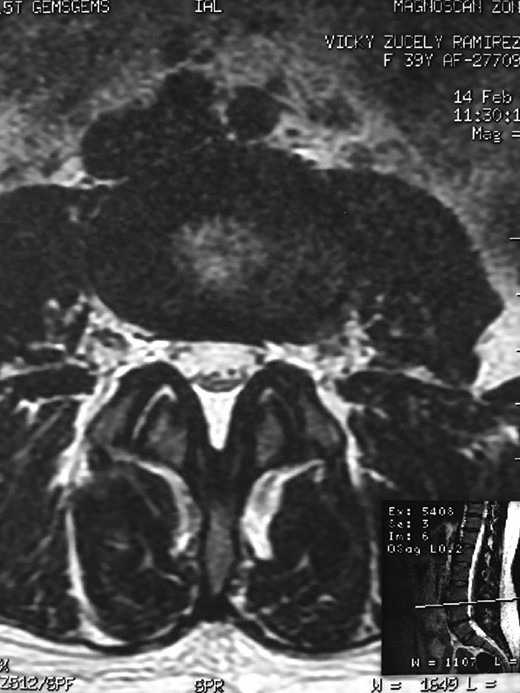

A 42-year-old female presented to the clinic with a history of chronic low back pain. She reported no relevant medical history. She had already been treated in the last 4 years by general practitioners with analgesics and home based physiotherapy with no satisfactory results. She had two previous admissions to the emergency department where morphine was prescribed to control the pain on her lower back. She was under ambulatory treatment with diclofenac, and tizanidine with partial relief of symptoms. Her main complaint was pain on the lower lumbar back with no radiation to the lower extremities. In her physical evaluation she presented limitation to full rotation and bending of the lumbar spine due to pain. Lasegue sign was negative, sensitivity, reflexes, sagittal balance, distal muscular strength and pulses were normal. Radiographs showed an overdeveloped left transverse process of the fifth lumbar vertebra which contacts with the sacrum at the left sacral wing with signs of degeneration at the same site (Fig. 1). Magnetic resonance imaging (MRI) studies were obtained (Figs 2–5). The patient was taken to the operating room where infiltration with 1 mL of lidocaine and 40 mg of Triamcinolone was performed in the pseudoarticulation between the left transverse process and the sacrum under fluoroscopic guidance. She reported a complete relief of pain after the procedure. At three months follow-up she was managed with strengthening and stabilizing exercises for the lumbar spine and postural education was initiated. She remains asymptomatic at her 12 months follow up.

Showing the protective effect of the limitation of the motion in the distal disc to the anomaly.

The partial fusion at the lower part of the lumbosacral transition produces important alterations in normal biomechanics at the levels immediately above and below the LSTV. Changes such as hypermobility and abnormal torque moments are present at the level above the LSTV, predisposing it to early degeneration (early disc pathology and facet joint degenerative disease). Restricted movement below the LSTV produces a protective effect against degeneration of disc and facets and is related to changes (facets are smaller and coronally oriented) in the dimensions of the lower level facet joints [7]. These alterations can be verified in the adjacent levels of the LSTV in our patient.